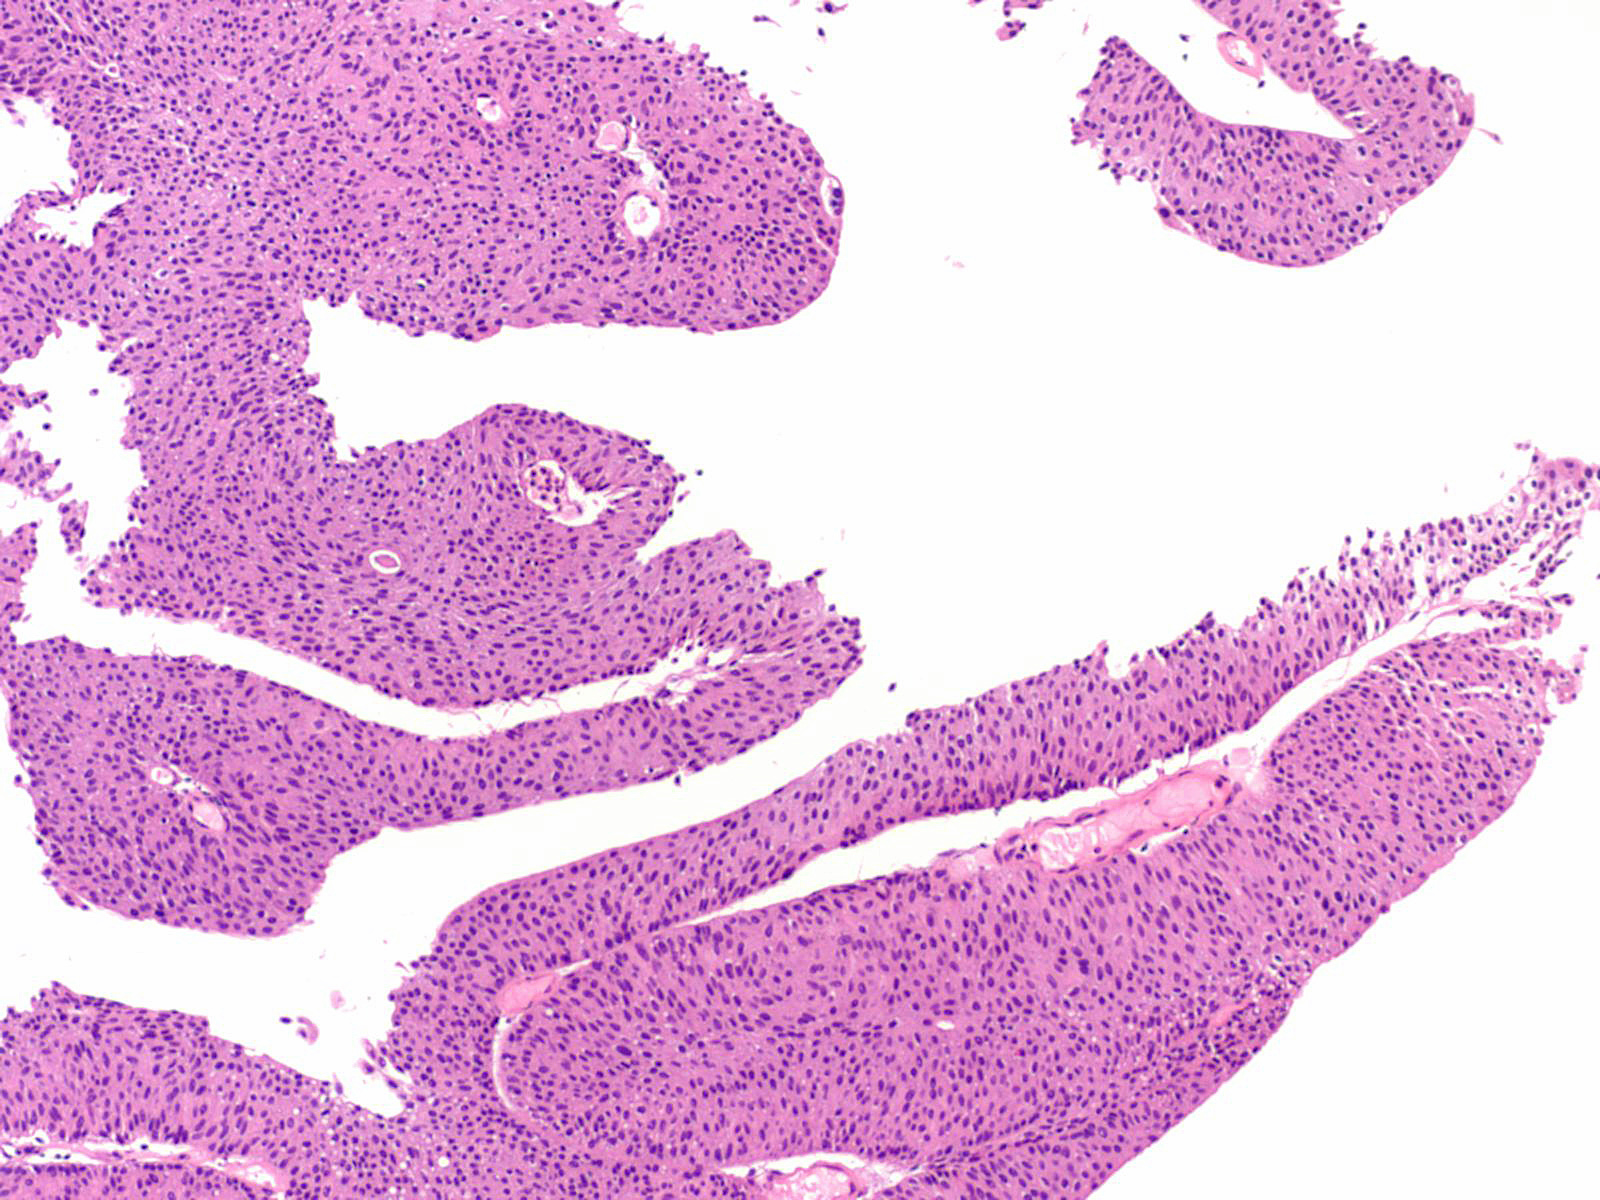

Consensus grade: Low-grade papillary urothelial carcinoma (LG-PUC)

Lesion shows moderate variation in nuclear size, shape and chromatin. Scattered nuclei are significantly enlarged and hyperchromatic relative to other nuclei. Lesion still maintains an overall orderly appearance.